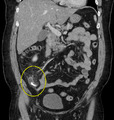

A fecalith is a stone made of feces. It is a hardening of feces into lumps of varying size and may occur anywhere in the intestinal tract but is typically found in the colon. It is also called appendicolith when it occurs in the appendix and is sometimes concomitant with appendicitis.[1] They can also obstruct diverticula. It can possibly form secondary to fecal impaction. A fecaloma is a more severe form of fecal impaction, and a hardened fecaloma may be considered to be a giant fecalith. The term is from Greek líthos=stone.[2]

A small fecalith is one cause of both appendicitis and acute diverticulitis.